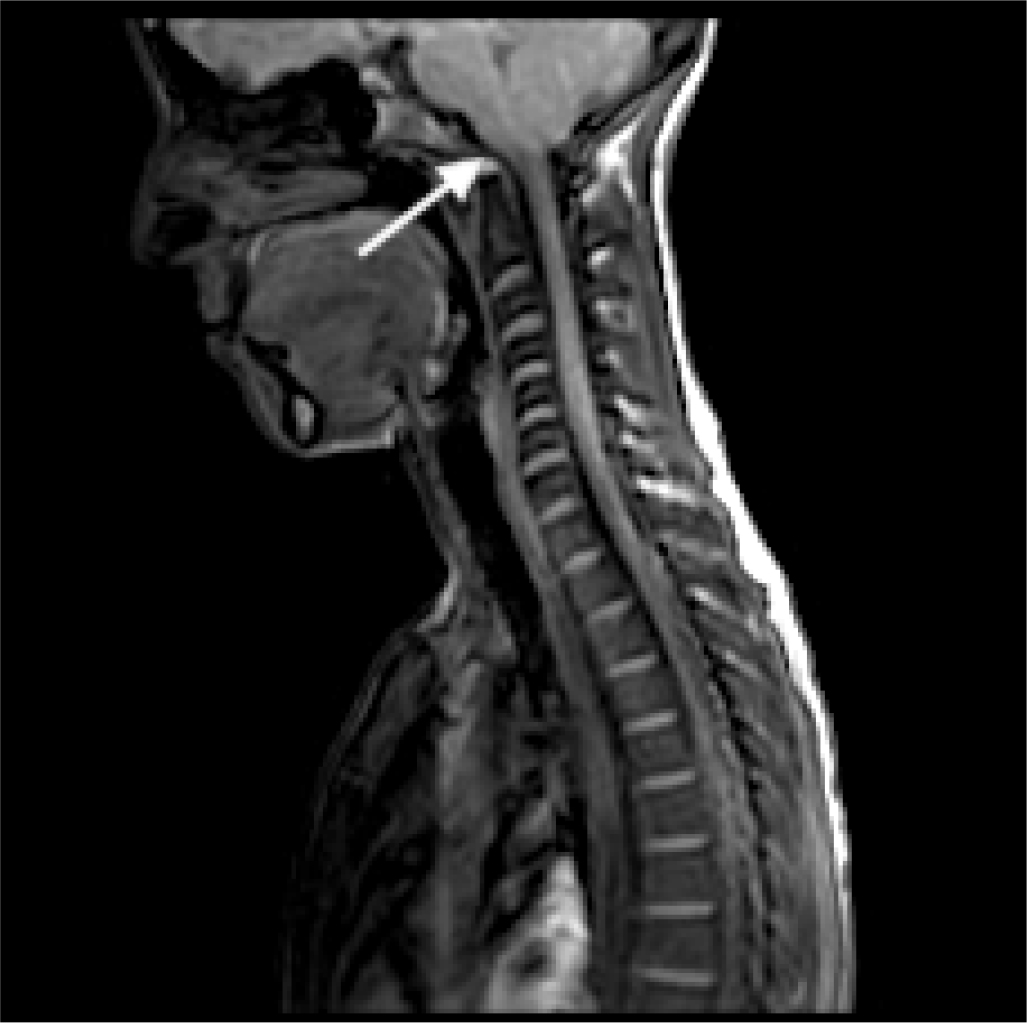

At the age of 14 years, the patient experienced pain in the right forearm and reduced sensitivity in the right hand. Since the symptoms persisted, the patient underwent a neurologic evaluation that did not find cranial nerve deficits in strength, function, or coordination, and symmetrical reflexes were evoked at all four limbs. An electroneurographic study was performed with negative results. For persistent hypoesthesia in the arm and right hand, three years after the onset of the first symptoms, the patient underwent a cervical magnetic resonance imaging (MRI), which showed hypoplasia of the basiocciput and a small posterior cranial fossa, with descent of the cerebellar tonsils through the foramen magnum for a maximum distance of about 1 cm. A significant hydro-syringomyelic cavity was observed extending from the cranio-cervical region up to a plane passing through D10-D11, with a more evident finding in the mid-dorsal site (Fig. 1). The patient underwent occipito-cervical decompression surgery with coarctation of the cerebellar tonsils and autologous duroplasty with postoperative significant improvement of syringomyelia.

Fig. 1 - Magnetic resonance imaging showing significant hydro-syringomyelic cavity extending from the cranio-cervical region up to a plane passing through D10-D11 in case 1.